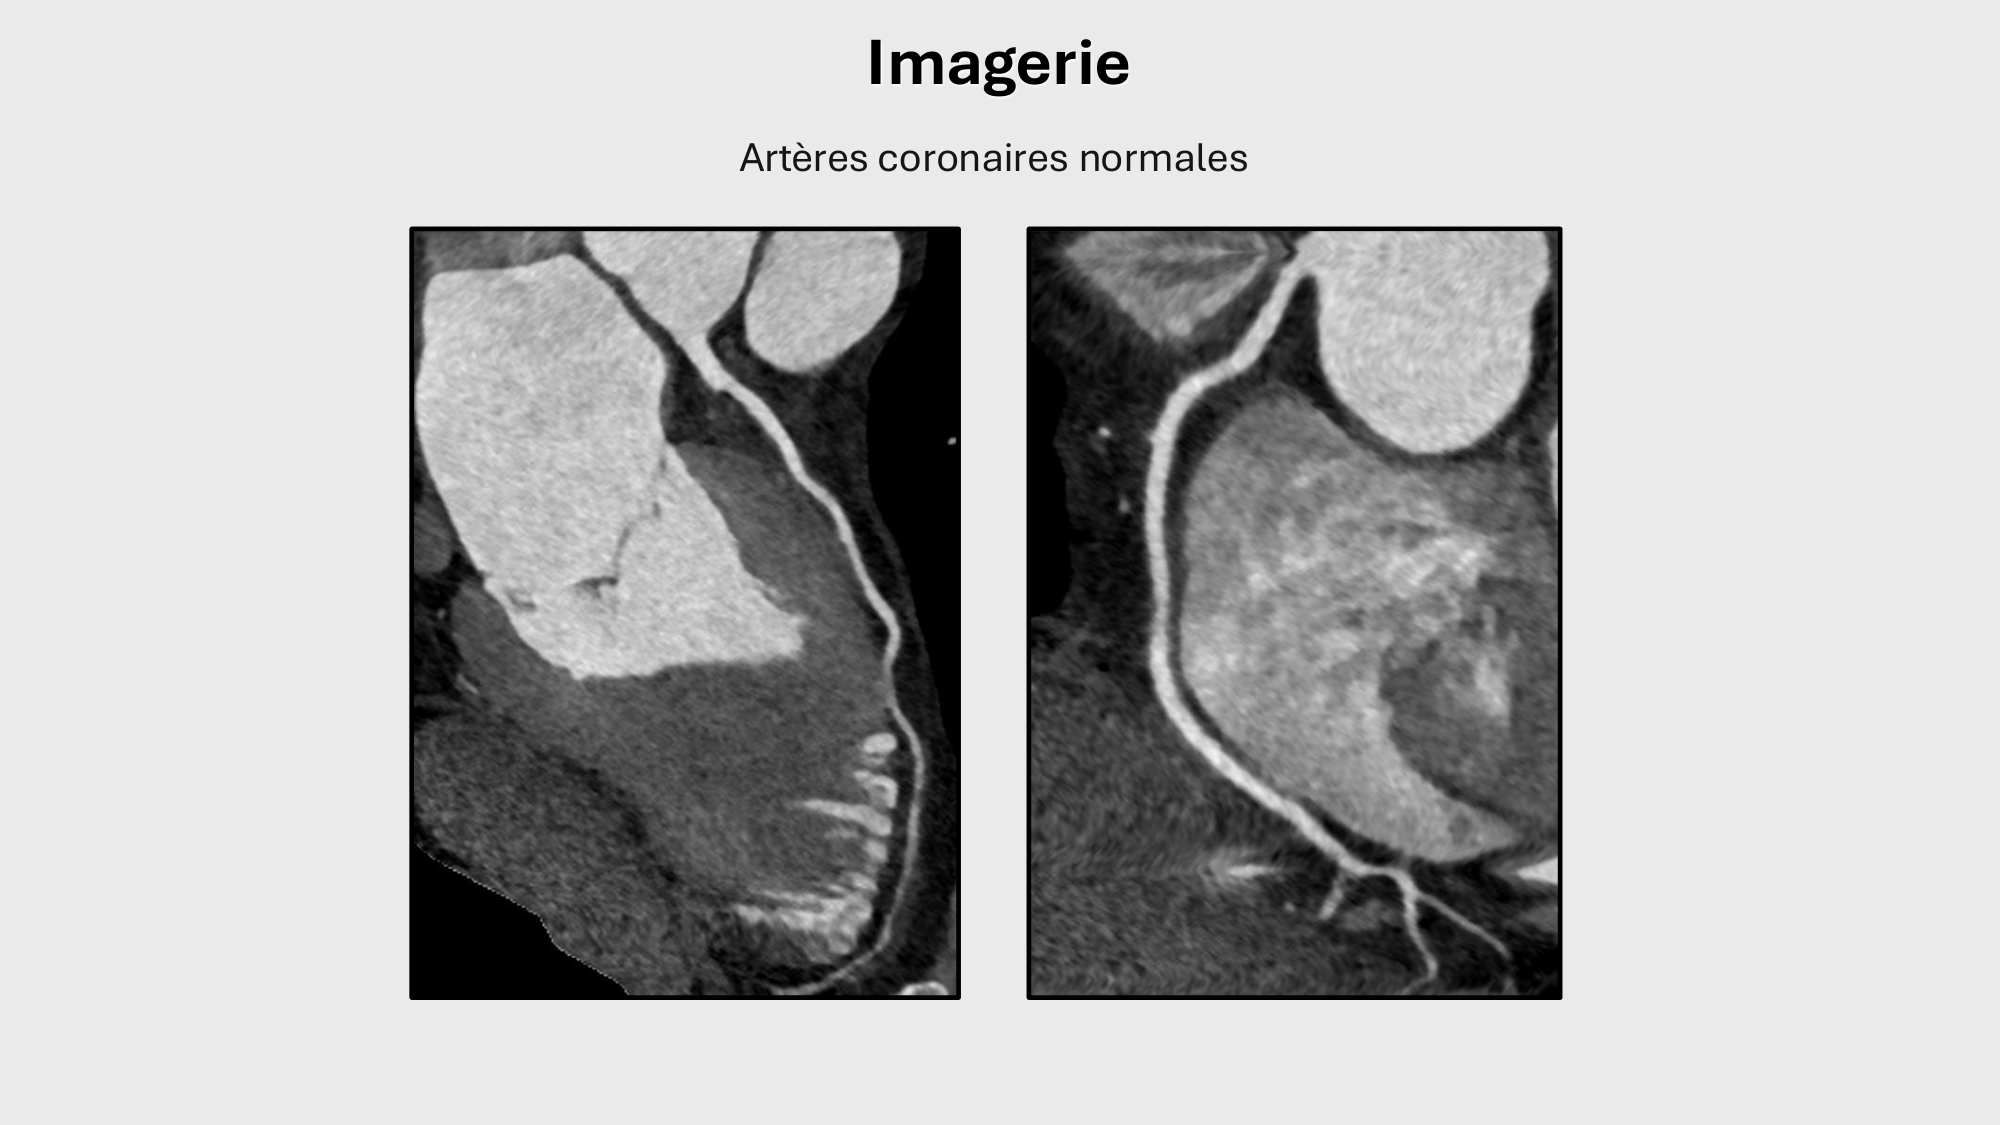

01.12 · F-Mach-Cas de-liaison-Athero-1-2025

F-Mach-Cas de-liaison-Athero-1-2025

Atherosclerosis series · 61 pages · 8 sections